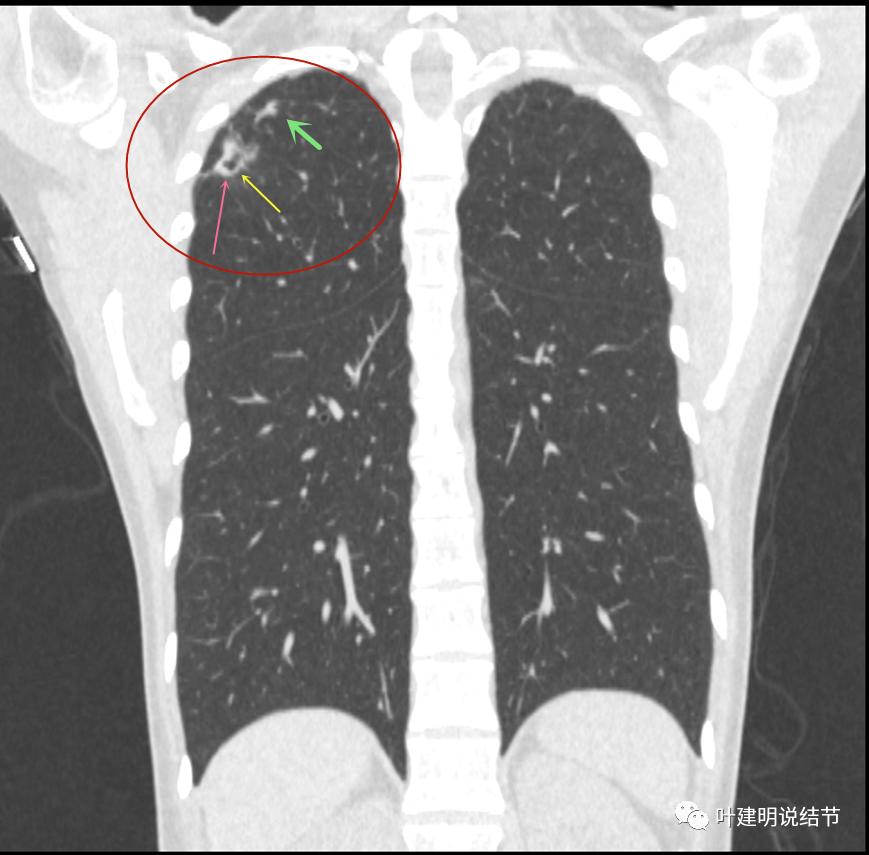

上面是她提供的病史资料,其中最重要的是PPD强阳性!其他主要看影像,我们先来看她2020年7月份的平扫片子(由于片子较多,详细展示是为了同道分析,我在影像特征描述上将只选取部分加以说明):

右肺尖偏实性结节(粉色箭头),邻近胸胸膜明显增厚不平,且广基附在胸壁上(蓝色箭头)

有卫星病灶(绿色箭头)